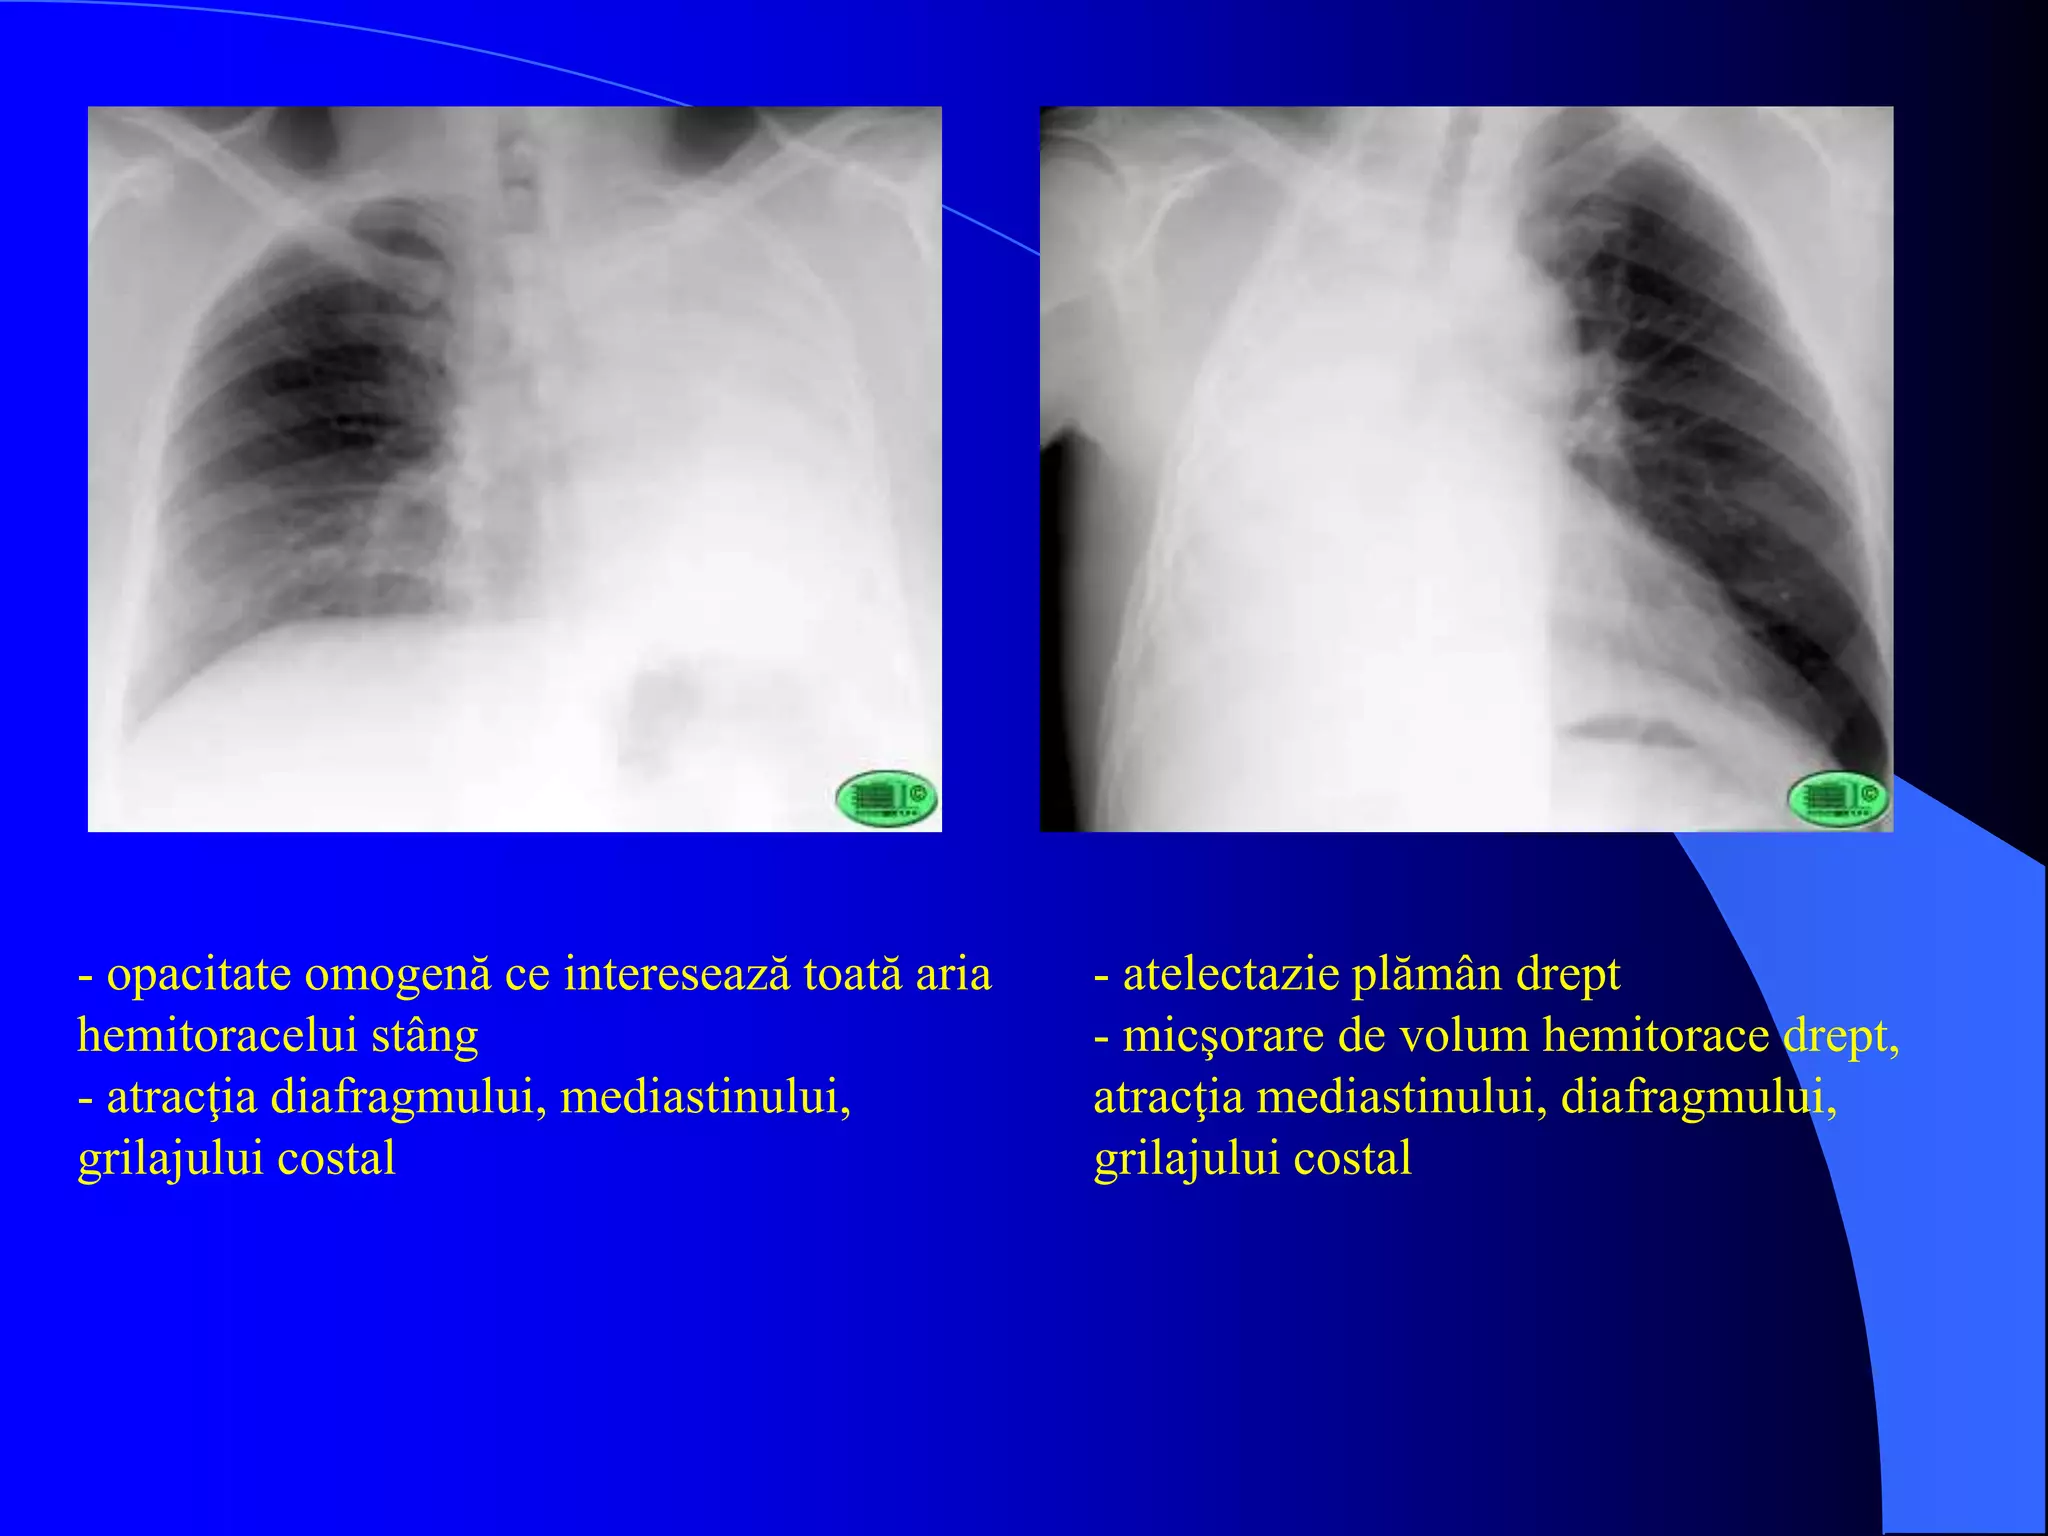

- opacitate omogenă ce interesează toată aria

hemitoracelui stâng

- atracţia diafragmului, mediastinului,

grilajului costal

- atelectazie plămân drept

- micşorare de volum hemitorace drept,

atracţia mediastinului, diafragmului,